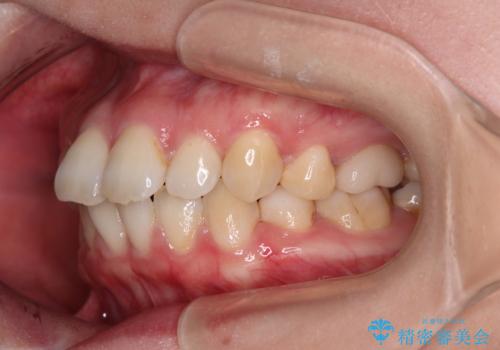

- 上下前歯の後戻りを気にして来院された患者様です。

インビザラインでの治療を希望されていて、デコボコの程度が中等度であり、安価なパッケージにて対応可能と判断されたため、インビザライン・モデレートを用いて矯正治療を行うこととしました。